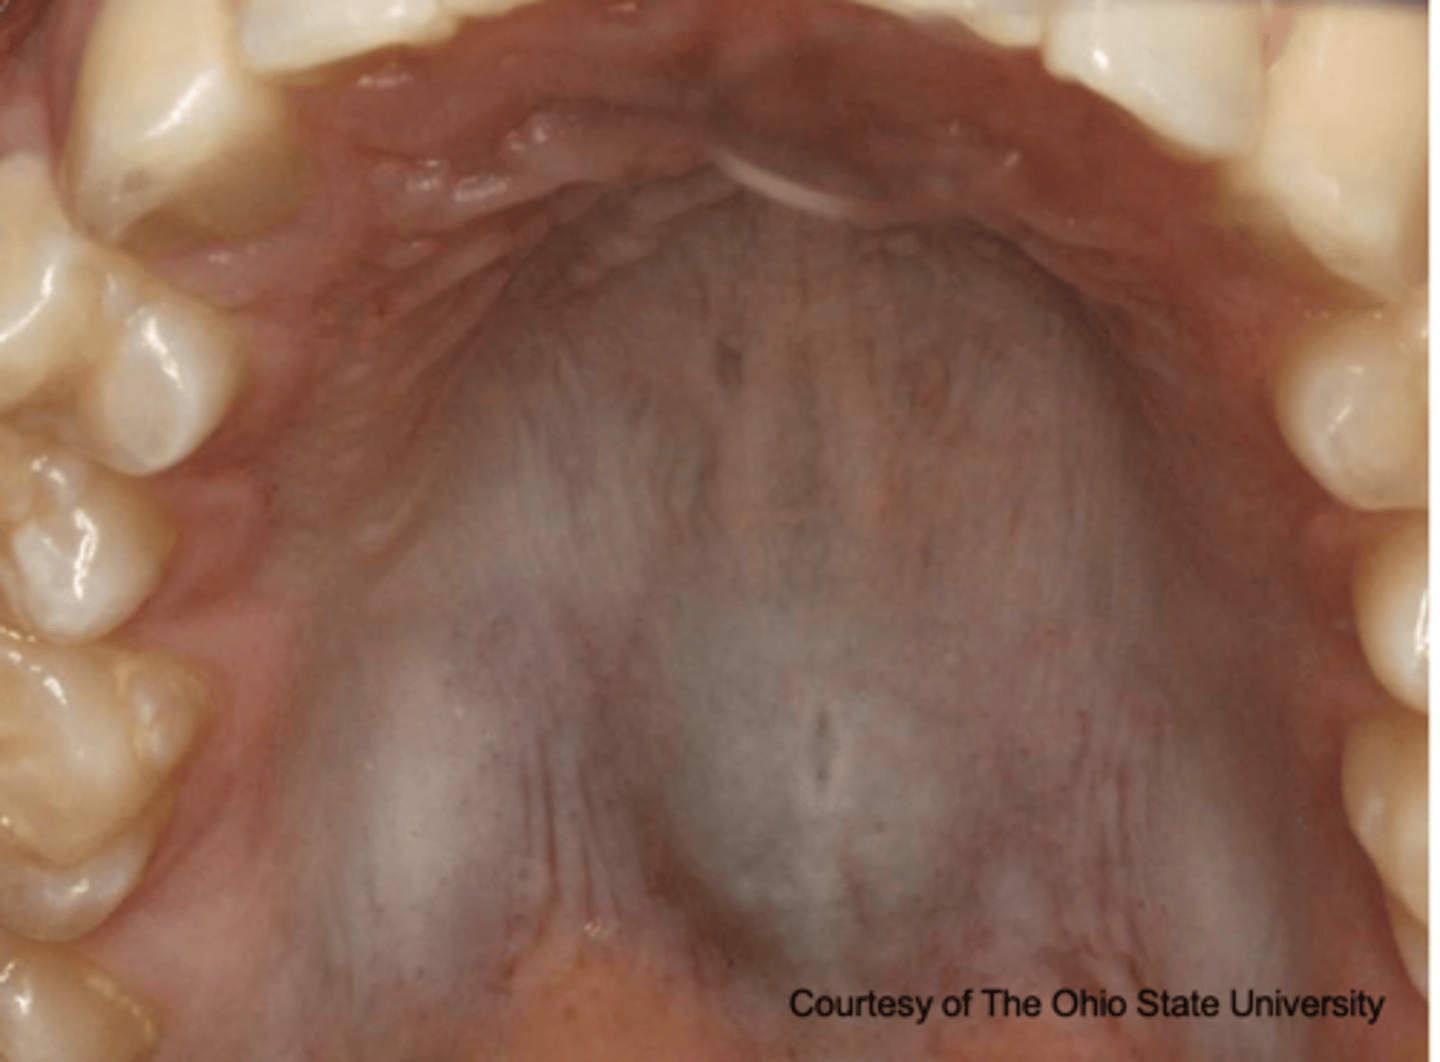

What type of pigmented lesion?

- Rare acquired pigmented lesion(s) of rapid onset

- Reactive?

- May reach several cm in size

oral melanoacanthosis (a.k.a. oral melanoacanthoma)

Oral Melanoacanthosis has a predilection for which ethnic group and which gender?

African American females

Oral Melanoacanthosis usually appears at which age?

3rd-4th decades

What is the differential diagnosis?

45 year-old African American female presented with this asymptomatic lesion for 2 months.

oral melanoacanthosis